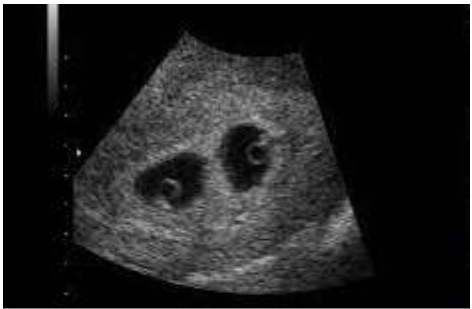

Paciente com 32 semanas de idade gestacional foi encaminhada para realização de ultrassonografia obstétrica, onde aparentemente observa-se uma placenta, dois fetos e duas cavidades amnióticas. Ela realizou um exame de ultrassom com 7 semanas de gestação em consultório, porém só possui as imagens.

Com base na foto abaixo, assinale a afirmativa correta: